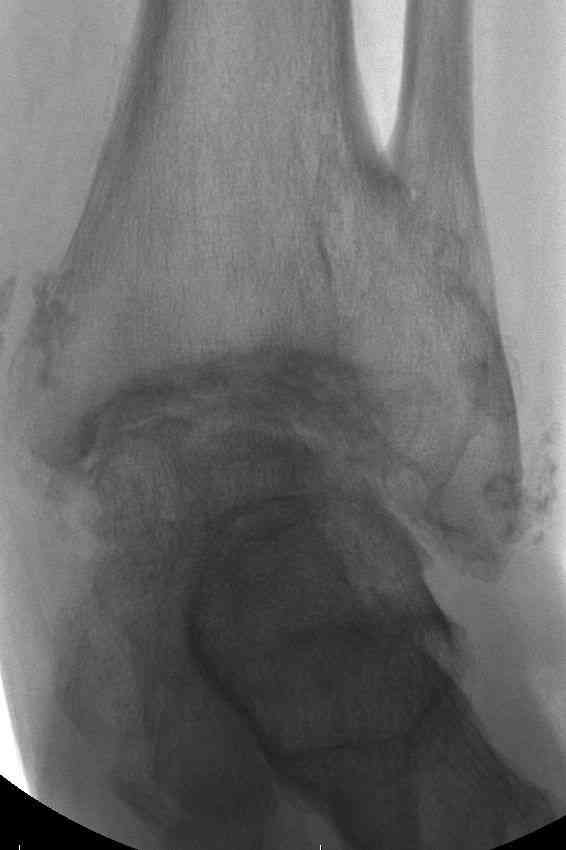

Эндопротезирование или артродезирование ?К нам обратился пациент 73 лет с жалобами на боли и деформацию в области левого голеностопного сустава. В анамнезе: в 1980 году перелом обеих лодыжек с вывихом стопы кнаружи. Лечился консервативно: одномоментная репозиция переломовывиха в левом голеностопном суставе с трансартикулярной фиксацией голеностопного сустава спицами Киршнера через пяточную, таранную, большеберцовую кости. Накладывалась гипсовая иммобилизация. Даная манипуляция осложнилась нагноением с развитием гнойного артрита. Были удалены спицы, сустав со слов больного, промывался растворами, но не вскрывался, получал антибиотики. Гнойный процесс был купирован, и рецидива с тех пор не было.Об-но: Левый голеностопный сустав деформирован за счет разрастания костной ткани и отечности мягких тканей. Левая стопа с вальгусной установкой, практически отсутствуют все своды левой стопы (стопа плоская). Полный объем движений в левом голеностопном суставе максимум достигает 15 гр, движения стопы в основном за счет подтарнного сустава. Пальпаторно область голеностопного сустава не столь болезненна, как болезненна область подтаранного сустава и область таранно-ладьевидного сустава.После изучения объективного статуса, анамнеза, рентгенснимков, больному предложен был трехсуставной артродез, так-как мы сочли это наиболее приемлемым в данном случае. Но больной отказывается от данной операции и настаивает на эндопротезировании левого голеностопного сустава. Во первых, наше отделение не имеет опыта в эндопротезиовании голеностопного сустава. Во вторых, нам кажется, что трехсуставное артродезирование в данном случае наиболее подходящее. Причиной тому, на наш взгляд, выраженная деформация левой таранной кости, как следствие аваскулярного некроза, и то что болит не голеностопный сустав в данном случае ( хотя в нем и ограничено движение), а подтранный и таранно-ладьевидный суставы и то что эндопротезирование одного голеностопного сустава не решит проблем в подтаранном, ладьевидно-таранном сочленениях. Наши доводы оказались безуспешными, а так как пациент является ученным, требовал доказательной базы наших умозаключений. Ваше мнение по данному случаю, и мы были бы благодарны, если у кого то есть материал по данной теме или есть ссылки. Заранее благодарны всем, кто примет участие в обсуждении данной темы.

По всем канонах хирургии стопы асептический некроз таранной кости - абсолютное противопоказание для эндопротезирования голеностопного сустава.